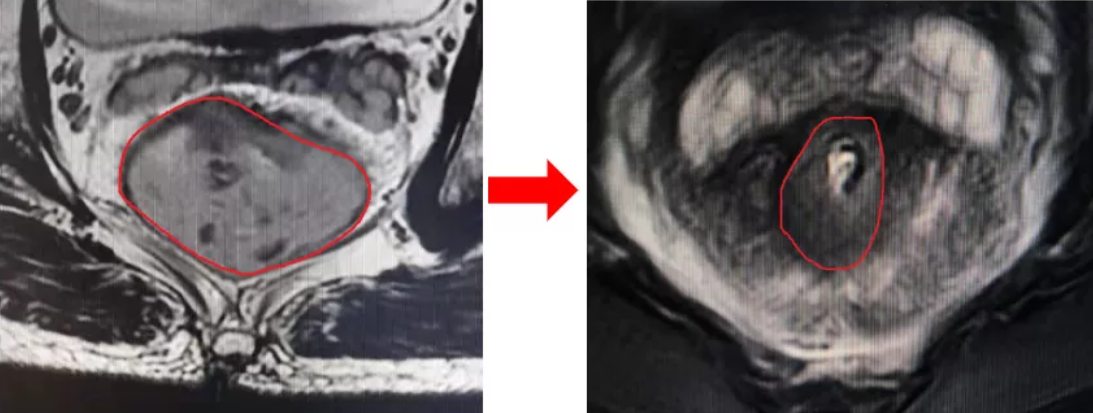

曾林随即转入肿瘤科,从8月份开始接受术前同步放化疗,放疗结束后复查磁共振发现肿瘤较前明显缩小。

在手术的过程中,我们欣喜地发现肿瘤明显退缩,已经达到了保肛的必要条件。